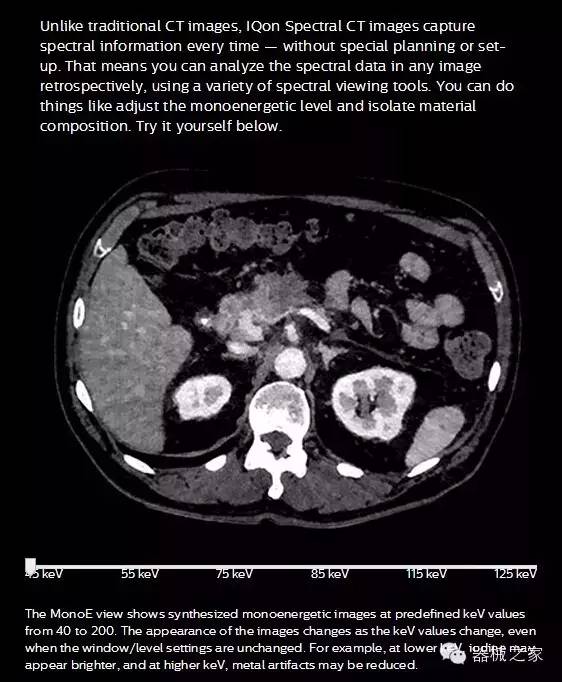

IQon光譜CT能夠按照需求提供光譜量化和工具,并能通過簡單工作流程、在低劑量下對(duì)結(jié)構(gòu)進(jìn)行定性分析

IQon光譜CT -- 是業(yè)界首臺(tái)以探測(cè)器為成像基礎(chǔ)的光譜CT,它可以在單次常規(guī)掃描下獲得傳統(tǒng)解剖影像及光譜功能影像。不僅可以提供精準(zhǔn)的診斷信息,還可簡化工作流程、在低劑量下完成定量與定性分析。